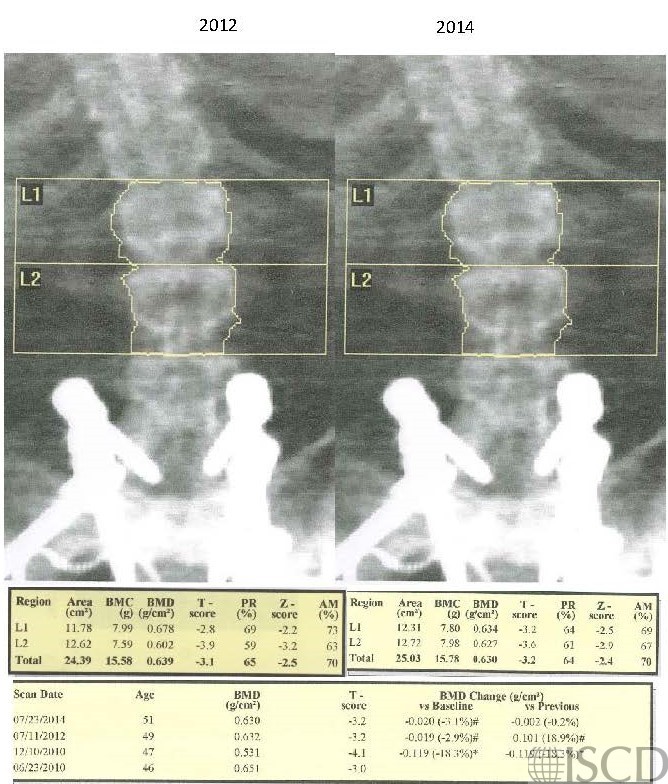

This is a baseline and follow-up scan of an individual with hardware at L3-L4. In this follow-up scan, the rods are not mapped, because autolow was forced during the comparison.

The spine hardware is included within the global region of interest scanned in the spine in both scans.

In this reanalysis of the scan, L3 and L4 are completely removed from the spine global region of interest scanned. Notice the difference in the interval change between 2012 and 2014.

The interval change of L1-L2 was affected by removing L3 and L4 with hardware from the global spine ROI. With the hardware in the ROI it indicates that there is an 88.2% loss since the previous scan. With the hardware removed from the ROI, there is stability in bone density from the previous scan. The rods did not map because AutoLow was forced with the compare scan. The normal analysis, which assumes nothing about the shape of the object, would have found the rods and they would have mapped.